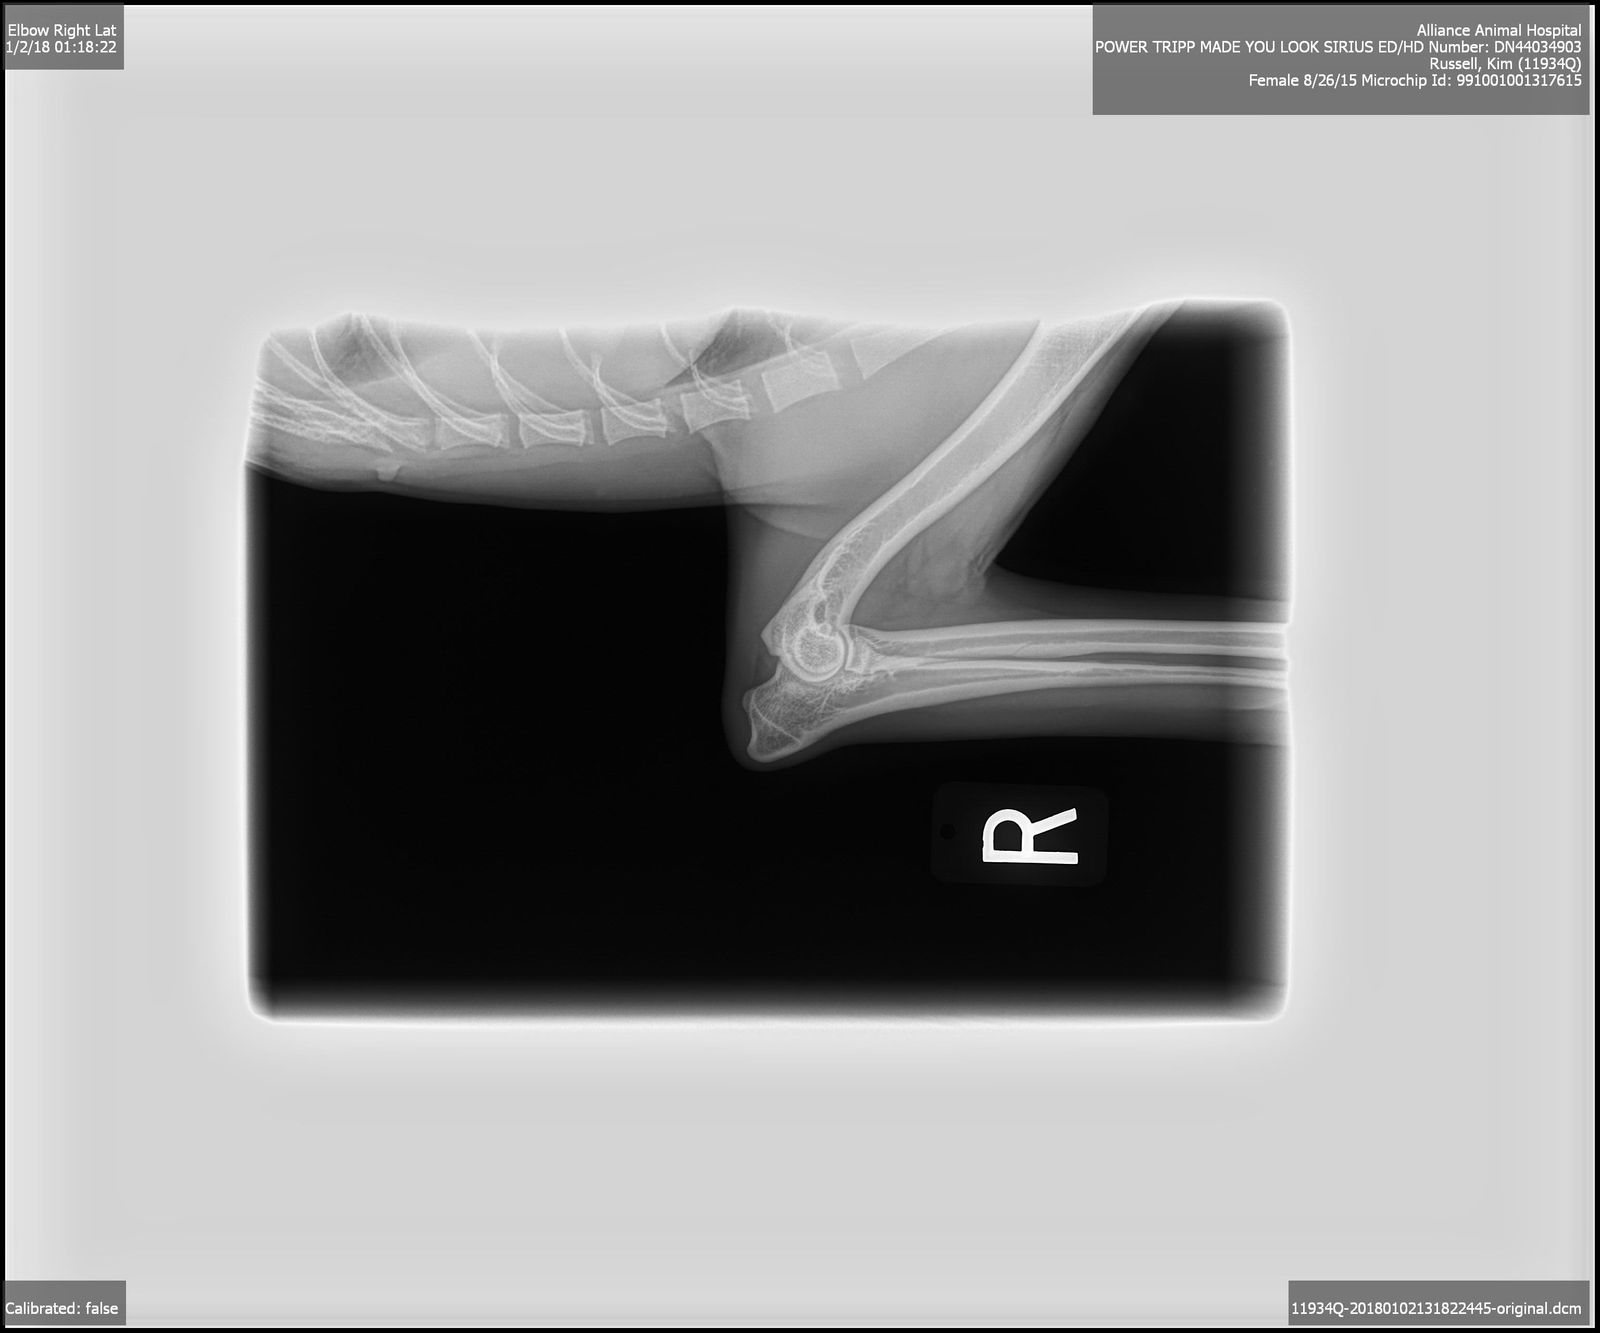

OFA Excellent, Shoulders and Elbows Normal, CEA/EAOD/CM/DM/MDR1/TNS/IGS/SN Normal,

2015/8/25AKC DN44034903 OFA Excellent, Shoulders and Elbows Normal, CEA/CM/DM/MDR1/TNS/IGS/SN Normal, BAER Normal